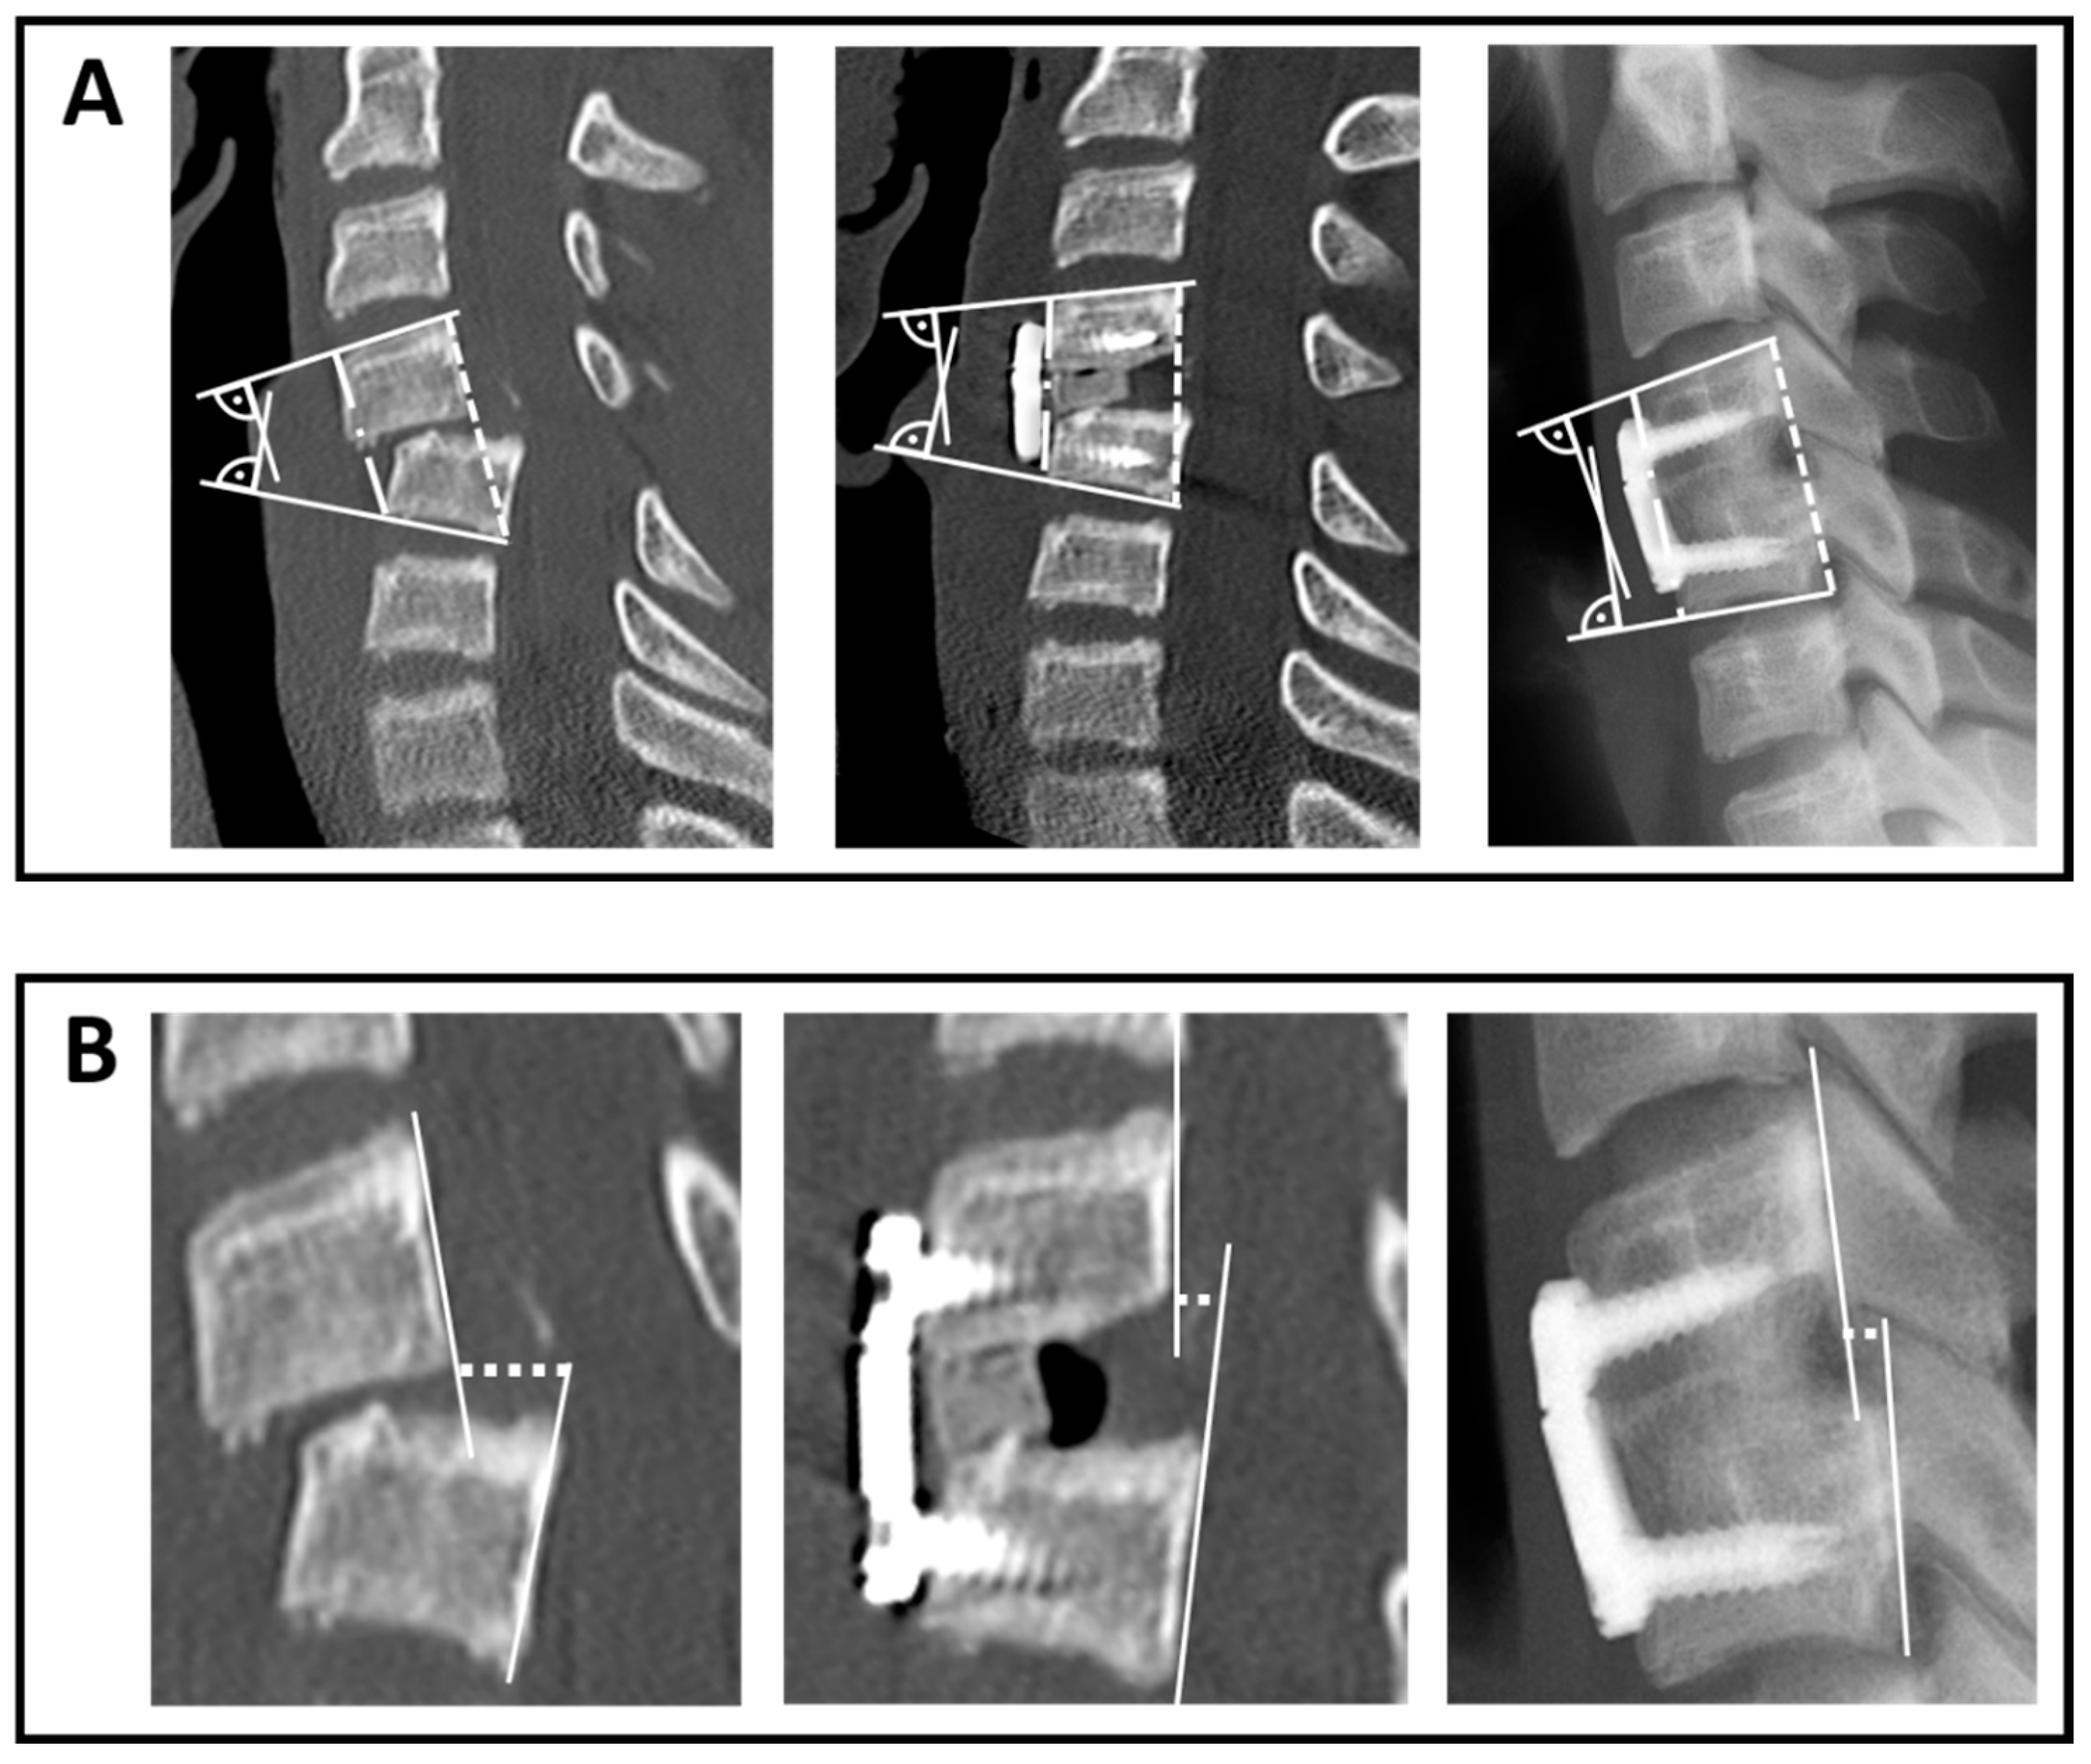

2.2. Radiographic Assessment

3.5.1. Reduction and Loss of Reduction in Terms of mEA and bEA

3.5.2. Anterior Translation